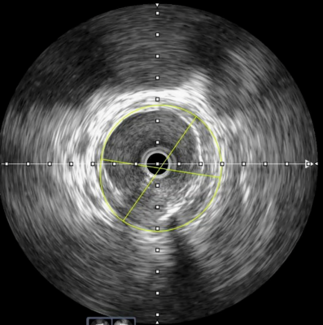

Muhammad Imran Hanif, MBBS, FCPS, FSCAI, FRCP; Muhammad Sikandar Saleem, MBBS, FCPS; Muhammad Ansar Maqsood, MBBS, FCPS

The authors share a case of complex wire entrapment during left anterior descending percutaneous coronary intervention illustrating the role of intravascular ultrasound in directing a bailout strategy.